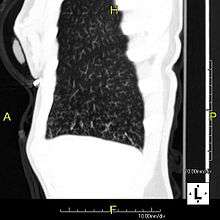

Tree-in-bud sign

In radiology, the tree-in-bud sign is a finding on a CT scan that indicates some degree of airway obstruction.[1]

The tree-in-bud sign is a nonspecific imaging finding that implies impaction within bronchioles, the smallest airway passages in the lung. The differential for this finding includes malignant and inflammatory etiologies, either infectious or sterile. This includes fungal infections, mycobacterial infections such as tuberculosis or mycobacterium avium intracellulare, bronchopneumonia, chronic aspiration pneumonia, cystic fibrosis or cellular impaction from bronchovascular spread of malignancy, as can occur with breast cancer, leukemia or lymphoma.[2] It also includes lung manifestations of autoimmune diseases such as Sjogren's syndrome or rheumatoid arthritis.[3][4]

Histopathologic studies have shown that the tree-in-bud pattern is caused by demarcation of the normally invisible branching course of the peripheral airways, which usually results from bronchioles being plugged or blocked with mucus, pus or fluid. In addition, dilated and thickened walls of the peripheral airways and peribronchitis can make the affected bronchioles more easily visible, as is seen in patients with cystic fibrosis.